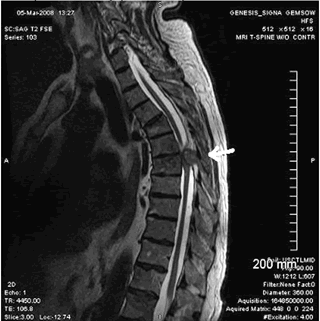

Магнитно-взвешенное изображение (MPT).

T1-взвешенное изображение:

- Непрерывный оссификат расположенный кзади от тел позвонка, распространяющийся на сагиттальных изображениях на несколько уровней.

- Характерный вид ЗПС а виде «перевернутой буквы Т» или «галстука бабочки» на аксиальных изображениях.

- Сигнал обычно отличается низкой интенсивностью во всех режимах исследования

- При значительном объеме жирового компонента в костно-мозговом пространстве оссификата интенсивность сигнала может быть гиперинтесивной.

Т2-взвешенное изображение.

- Картина ОЗПС схожа с картиной на Т1.

- Визуализация спинного мозга с наличием гиперинтенсивного сигнала коррелируется с миеломаляцией и отеком.